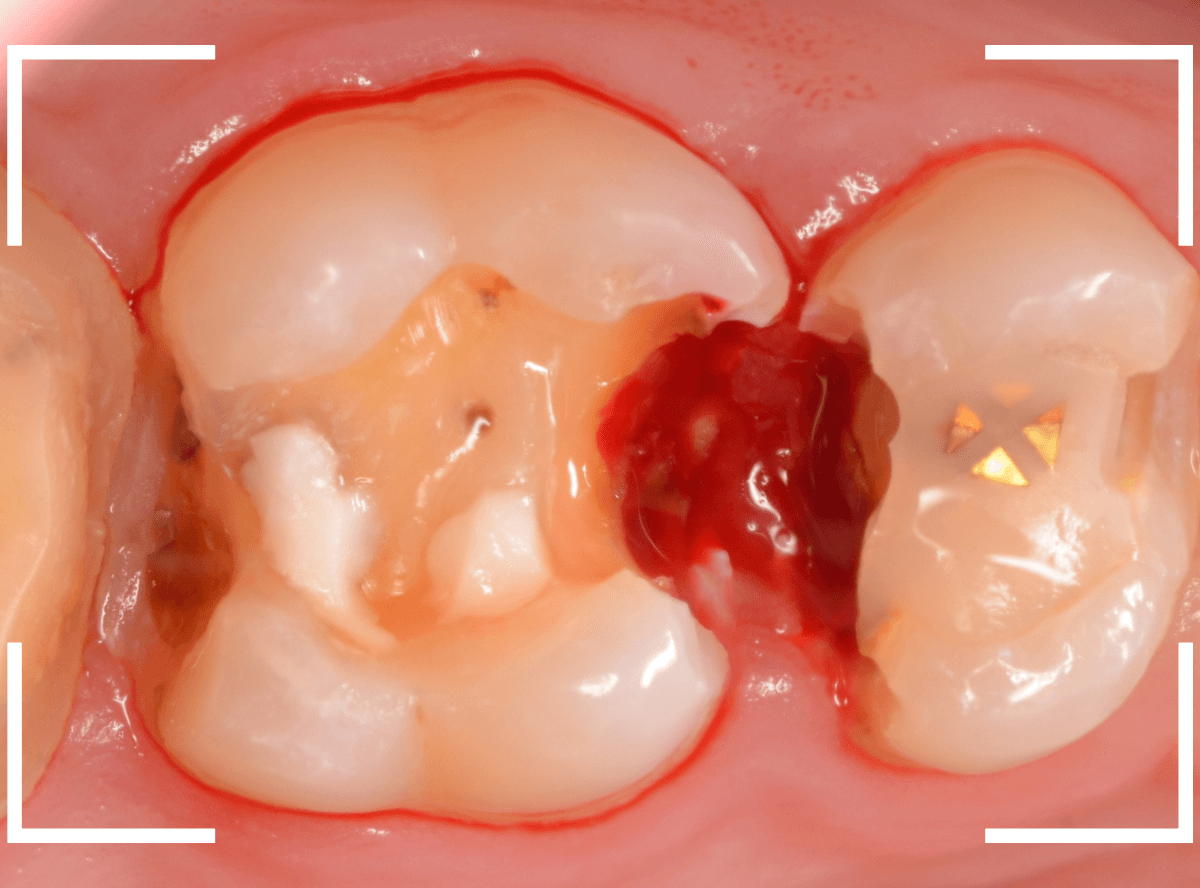

金属を外したところです。

写真では写ってしませんが、この奥に虫歯があります。

全ての虫歯を除去したところです。

抜歯した後ろのおやしらずは、元々虫歯の治療がしてありましたが、その際に抜歯しておいた方が良かったのではないかな、と思いました。